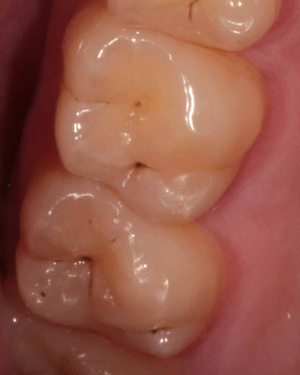

Для устранения разночтений в плане лечения в клиниках сейчас широко внедряется дентальная макрофотография, которая помогает врачу и пациенту объективно определить необходимость лечения или отсутствие последней. Разногласий с пациентами возникает гораздо меньше.

Инрооральные камеры начал применять одним из первых в Новосибирске.Итрооралкой фиксируется каждый этап лечения(акт скрытых работ). Но она не дает полномасштабной качественной картинки. Со временем, пришёл к выводу, что это дешевое дополнение к другим оптическим дивайсам.